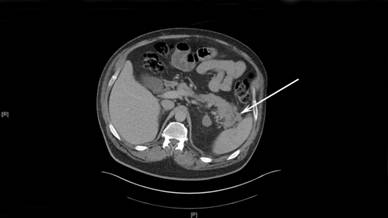

A 57-year-old man presented with abdominal pain and nausea. His past medical history included diabetes mellitus type 2, hypertension, and hypercholesterolaemia. The working diagnosis was a pancreatic tail adenocarcinoma. A locally advanced tail of pancreas mass with localised infiltration of the peritoneal reflection and descending colon mesentery with no evidence of distant metastases was shown on imaging (CT/MRI) (Figure 1). His CA 19-9 was within normal range. Following MDT discussion he proceeded to surgery where distal pancreatectomy, splenectomy, left colectomy and small bowel resection were performed. The histopathological report described a 47 x 45 x 30 mm necrotic mass with a palisading granuloma and vasculitis, predominantly involving the pancreatic adipose tissue with infiltration into the pancreas, the colon and splenic capsule. The small bowel specimen had only serosal fibrosis with adhesions to the adjacent connective tissue. No malignancy was identified and there was no lymph node involvement. Grocott staining for fungus and Ziehl-Neelsen staining for mycobacterium were negative. The combination of geographic necrosis, palisading granuloma and vasculitis was highly indicative of WG. The patient was ANCA negative, CT of facial sinuses and lung function tests were normal.

Figure 1. CT image depicting a bulky “soft tissue density” mass of the tail of the pancreas extending to the hilum of the spleen. The white arrow shows the mass. |